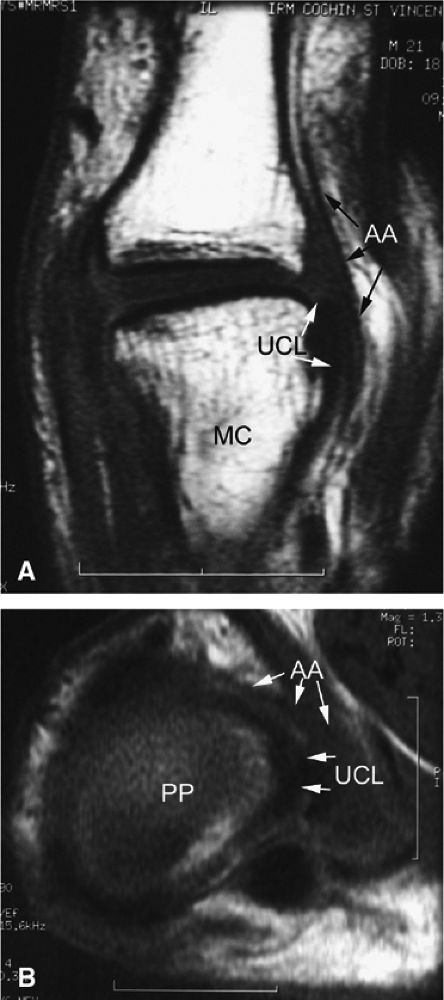

rotation. Stability is provided by the collateral ligaments, the volar plate, and musculotendinous elements. When the sesamoid bones are included in the volar plate, it is referred to as the volar complex (Fig. 11.4). On the medial aspect of the joint, the adductor pollicis is a strong insertion on the proximal phalanx and the volar plate, and contributes to the adductor aponeurosis. The ulnar collateral ligament (UCL) is covered dorsally by the adductor aponeurosis (Fig. 11.5).7,13

FIGURE 11.5 ● Coronal (A) and axial (B) T1-weighted images showing the ulnar collateral ligament (UCL) and adductor aponeurosis (AA). The UCL is deeper than the AA on axial images. On coronal images, the oblique AA is often more visible distal to the UCL. MC, metacarpal; PP, proximal phalanx.

|

The UCL lies deep to the overlying low-signal adductor aponeurosis on coronal images (Figs. 11.7 and Fig. 11.8). In a nondisplaced partial or complete tear of the UCL, the ligament appears thickened all along its course, sometimes with a small gap. When displaced, the UCL appears as a proximally retracted round or stump-like structure, which demonstrates low signal on all sequences. It is no longer parallel to the long axis of the thumb and presents an increased horizontal orientation.